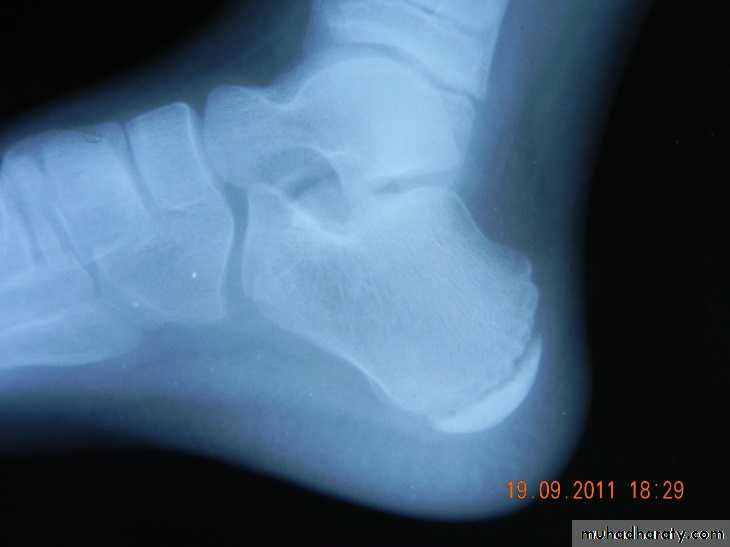

X-ray: boney spur.

Calcaneal spur